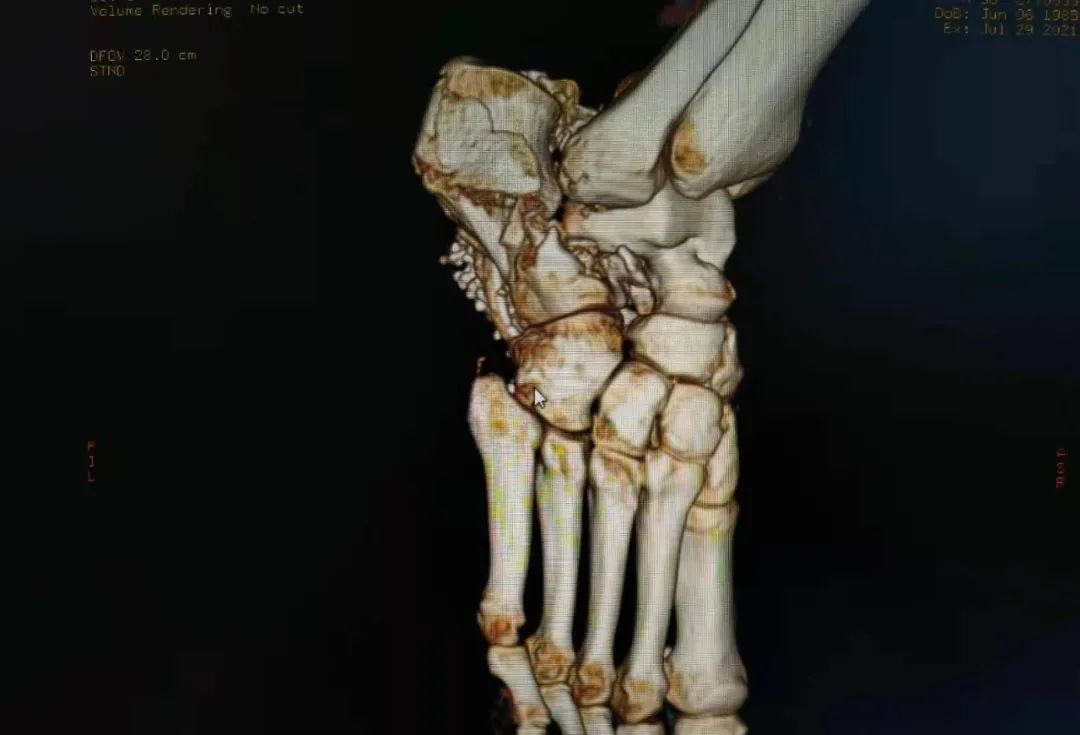

7月一天下午,东院急救中心接诊一名高空坠落的青年男性患者王某,入院时患者神志不清伴全身多处骨折出血,出现失血性休克并严重创伤性凝血病,多项指标均报危急值。东院急救中心立即开辟绿色通道,医护人员第一时间成立抢救小组,进行全方位研判、抢救。通过全身CT检查显示患者脑挫裂伤、双肺多发创伤湿肺、间质水肿、双肺胸腔积液并不张,右上腹游离气体影,考虑胃肠道穿孔,腹盆腔积液积血、腹膜后挫裂伤,胆囊胆汁淤积,右侧多发肋骨骨折,颈、腰锥体压缩性骨折,右侧肘关节、髂骨、股骨、胫骨及骶尾骨多发粉碎性骨折,右侧腰背部、臀部软组织挫裂伤、血肿形成。

术后经过严密的监护治疗,患者顺利度过了休克期、ARDS期、感染期。由于患者骨折多发且复杂,为最大限度帮助患者恢复正常生活,创伤中心首席专家周东生教授分四次完成了确定性功能修复手术。患者术后恢复良好,转入康复功能训练期。